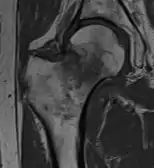

4) Данных рентгенологического обследования — выполняется рентгенография тазобедренного сустава в прямой проекции. Наличие линии перелома на рентгенограмме служит окончательным, объективным подтверждением предварительно выставленного диагноза. Иногда для постановки диагноза может потребоваться магнитно-резонансная томография или компьютерная томография.

В большинстве случаев достаточно выполнения рентгенограммы в прямой проекции. В ситуациях, когда есть подозрение на перелом шейки бедра, но оно не выявлено на рентгеновском снимке, следующим методом исследования является КТ. В редких случаях для подтверждения диагноза используется МРТ - диагностика.

Случай, демонстрирующий возможный порядок исследования изначально незаметных проявлений: